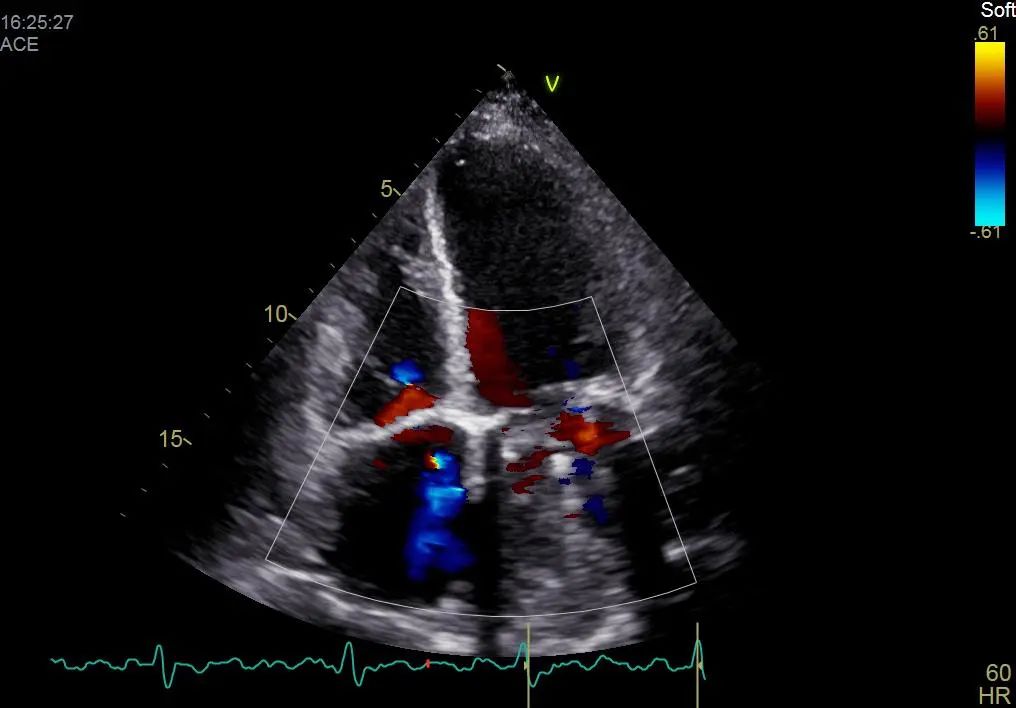

经过一段时间的对症治疗,患者症状有所缓解,但复查结果显示二尖瓣及三尖瓣仍为重度关闭不全,经心外科团队共同探讨,患者具备外科手术指征,决定在全麻体外循环下行二尖瓣置换术、三尖瓣成形术、左心耳缝合术 。术后患者恢复良好,现已治愈出院。

术后彩超影像